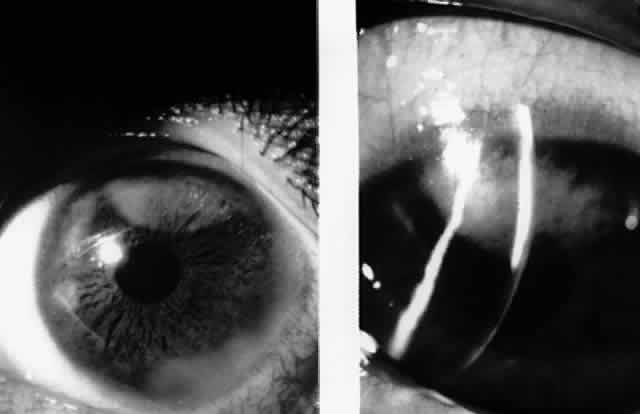

In 1986, Matoba and associates reported 7 patients with purported EBV stromal keratitis, but only 3 of the patients had clinical symptoms of IM or evidence of recent seroconversion.69 In one of the patients, heterophil antibody-positive IM preceded by 1 week the onset of chronic multifocal keratitis. When the authors first examined the patient in referral 9 months later, they found multiple, discrete, anterior stromal opacities in the patient's left eye. In another patient, bilateral, patchy, deep peripheral infiltrative keratitis and a fourfold decrease in antibody against EBV viral capsid antigen were documented at the time of referral 5 months after an “infectious mononucleosis-like illness” associated with bilateral red eyes and photophobia. In another patient, the authors state that IM preceded subepithelial infiltrative keratitis in the left eye by 1 month. When examined 8 months after onset of the keratitis, the patient's left cornea showed features of multifocal anterior stromal and deep peripheral stromal keratitis. Although the other 4 patients in this series did not show evidence of recent EBV seroconversion, their keratitis appeared similar to that of the patients with documented IM. On clinical grounds alone, Matoba and associates postulated that the development of EBV keratitis did not depend on recent EBV infection, but could occur in the chronic carrier state. To summarize the authors' findings in the combined group of 7 patients, the interstitial keratitis appeared in 4 patients as unilateral, multifocal, discrete, sharply demarcated, anterior stromal opacities, 0.1 to 2 mm in diameter, with either a blotchy pleomorphic (Fig. 2) or granular ringlike appearance (Fig. 3), in two patients as bilateral, multifocal, full-thickness or deep stromal peripheral infiltrates reminescent of luetic keratitis (Fig. 4), and in 1 patient with features of both. No patient tested had showed serologic evidence of acute systemic HSV or adenovirus infection. Both patients with keratitis restricted to the peripheral cornea had bilateral disease but lacked serologic evidence for syphilis (nonreactive MHA-TP). Five patients had mild or moderate corneal stromal vascularization. Two patients showed corneal epithelial granularity overlying the stromal opacities.

Fig. 2. Blotchy pleomorphic multifocal anterior stromal corneal infiltrates in a 25-year-old woman. (Matoba AY, Wilhelmus KR, Jones DB: Epstein-Barr viral stromal keratitis. Ophthalmology 93:746, 1986)

Fig. 3. Sharply demarcated ring opacities of the anterior corneal stroma in an 11-year-old boy. (Matoba AY, Wilhelmus KR, Jones DB: Epstein-Barr viral stromal keratitis. Ophthalmology 93:746, 1986)

Fig. 4. Multifocal deep peripheral corneal stromal infiltrates in a 17-year-old man. (Matoba AY, Wilhelmus KR, Jones DB: Epstein-Barr viral stromal keratitis. Ophthalmology 93:746, 1986)